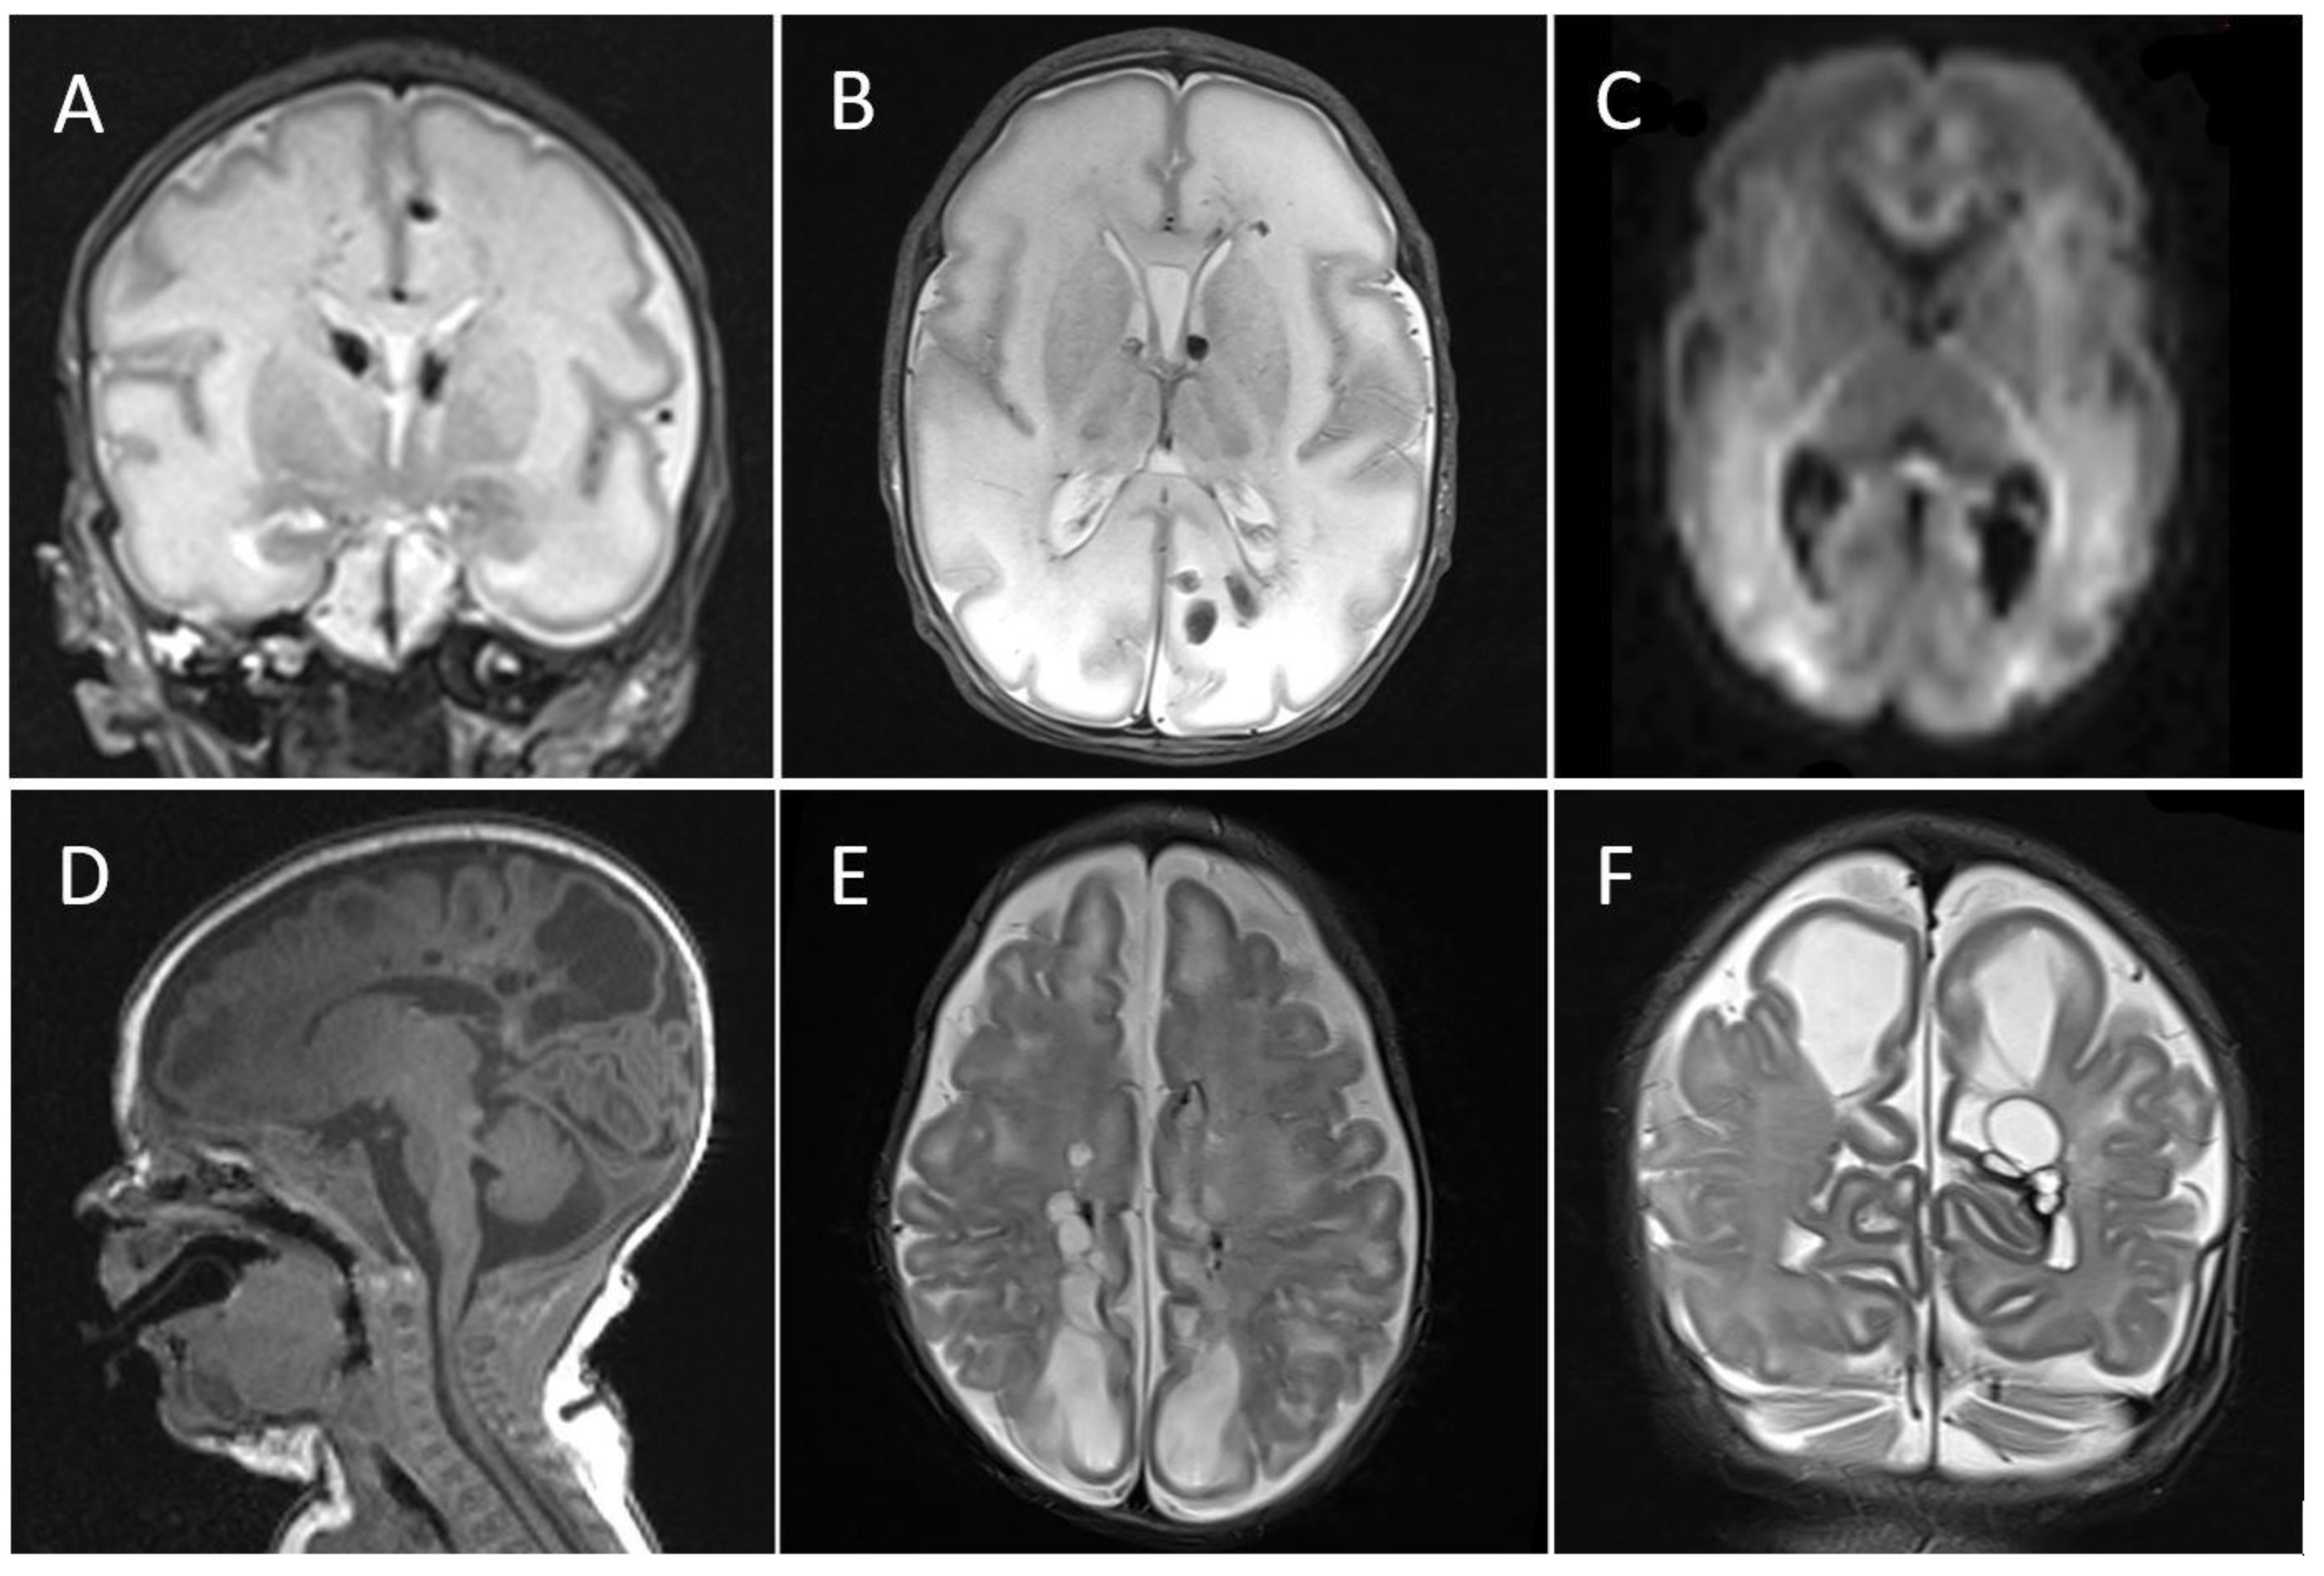

4.3.1. Case 1

4.3.2. Case 2